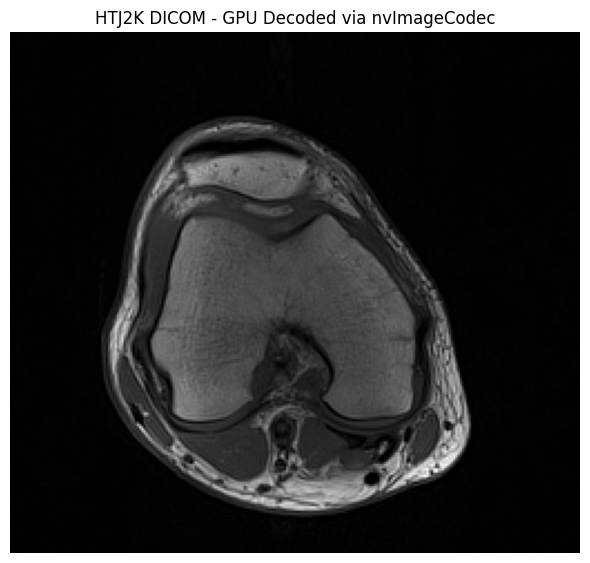

Decode with pydicom Plugin#

The HTJ2K datasets can be decoded using the pydicom plugin for GPU acceleration:

middle_slice = htj2k_datasets[len(htj2k_datasets) // 2]

print(f"Transfer Syntax: {middle_slice.file_meta.TransferSyntaxUID.name}")

print(f"Pixel Array Shape: {middle_slice.pixel_array.shape}")

print(f"Pixel Array dtype: {middle_slice.pixel_array.dtype}")

# Display the image

plt.figure(figsize=(6, 6))

plt.imshow(middle_slice.pixel_array, cmap="gray")

plt.title("HTJ2K DICOM - GPU Decoded via nvImageCodec")

plt.axis('off')

plt.tight_layout()

plt.show()

print("\n✓ GPU-accelerated decoding works seamlessly!")

Transfer Syntax: High-Throughput JPEG 2000 with RPCL Options Image Compression (Lossless Only)

Pixel Array Shape: (234, 256)

Pixel Array dtype: uint16

../_images/samples_DICOM-transcoding_8_1.png

✓ GPU-accelerated decoding works seamlessly!